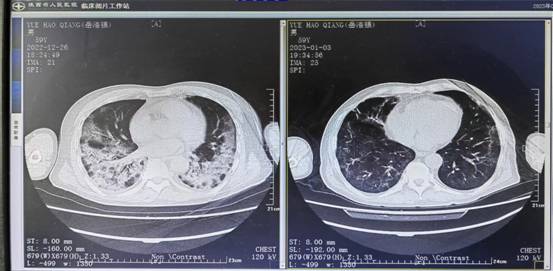

岳先生59岁,基础有2型糖尿病,入院时胸部CT显示“大白肺”,考虑新型冠状病毒感染(重型)I型呼吸衰竭,家属感到手足无措,急得像热锅上的蚂蚁。入院后呼吸重症三区医生结合患者病情,和家属充分沟通,为患者制定了全面的治疗方案:给予抗感染、抗病毒、抗炎、抗凝及营养支持等治疗,但患者治疗3天后复查胸CT仍显示肺部渗出进展明显,经过院内疑难危重病例讨论专家宗媛主任、杨淑梅主任等专家及魏益群主任会诊后调整治疗方案,加强免疫治疗并继续加强俯卧位通气治疗,李兴珍护士长及肖培芬护士长带领全体护士每日正确指导并鼓励岳先生做好俯卧位通气,经过重症三区全体医护人员的努力治疗,患者岳先生病情逐渐好起来,治疗10天后复查胸部CT明显好转,缺氧情况明显改善好转出院。岳先生出院时家属高度评价了呼吸重症三区医护团队专业技术及优质护理服务。家属说到呼吸重症三区医务人员的优质服务让病人放心、安心、舒心,自己身体的康复离不开每一位医护人员的精心呵护。